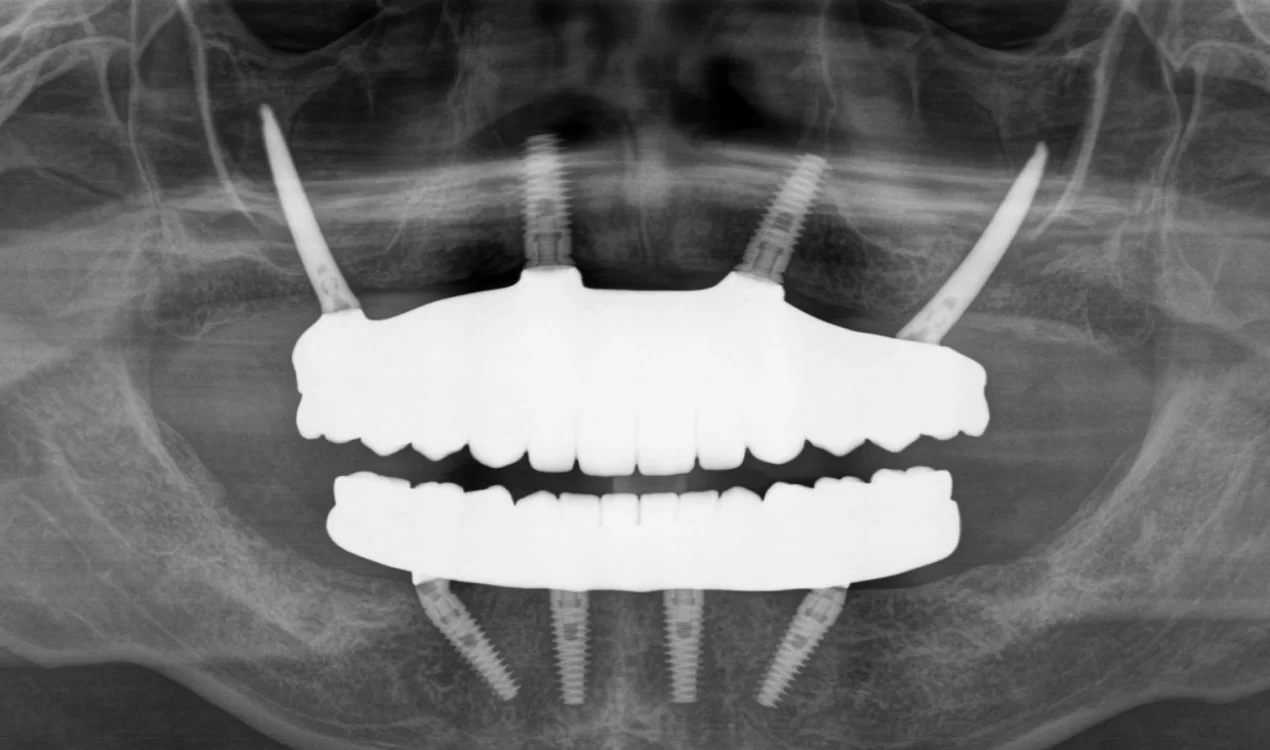

術前

術後

内容 :上下顎オールオン4ザイゴマ2

費用 :5,899,850円

※モニター価格

期間 :半年

リスク:出血・腫れ・痺れ・痛み